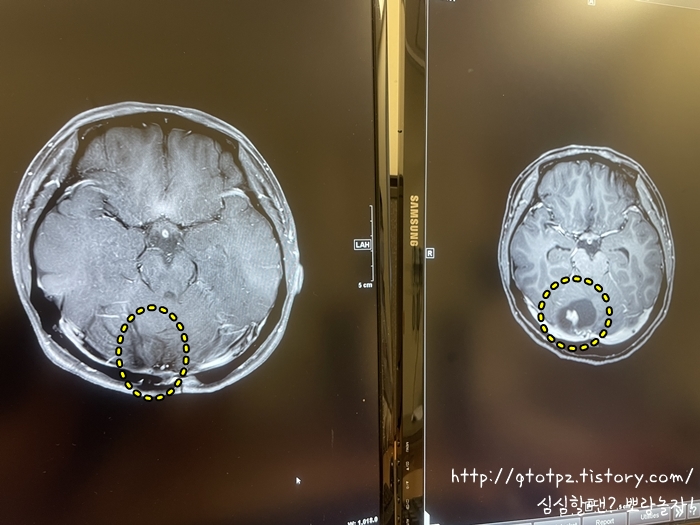

그러저러한 상황이 있었지만 들어가선 금방 끝났습니다. ㅋㅋ 혈관모세포종 투병일기 아마 마지막 포스팅이 될 것 같아요. 긴 여정에 마침표를 찍었습니다. 이제 더 MRI 찍으면서 관찰할 필요가 없다구 합니다. 정상인이 되셨다고. 음. ㅋㅋㅋ 산정특례기간이 5년이라 아직 2백여 일 남았는데 쿨하게 괜찮다고 하시네요. 수술 한 흔적만 남았다고 하셔요. 그래서 비교 사진을 찍어보았습니다. ㅋㅋㅋ 왼쪽이 2021년, 오른쪽이 2017년이에요. 제 눈에도 괜찮아 보이는 것이 오옷. 이제 끝이구나! 벅찼어요.